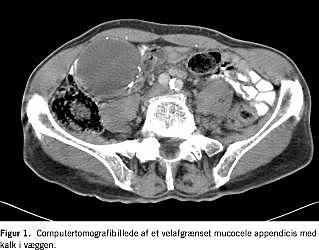

En supplerende Dopplerundersøgelse viste ikke øgede Dopplersignaler. Ved en computertomografi (CT) bekræftedes fundet (Figur 1 ). Ved laparotomi blev der fundet en makroskopisk benign, mobil tumor, beliggende i appendix 2,5 cm fra basis af appendix. Der blev foretaget appendektomi. Det postoperative forløb var ukompliceret. En mikroskopi viste mucocele uden malignitetssuspicio.